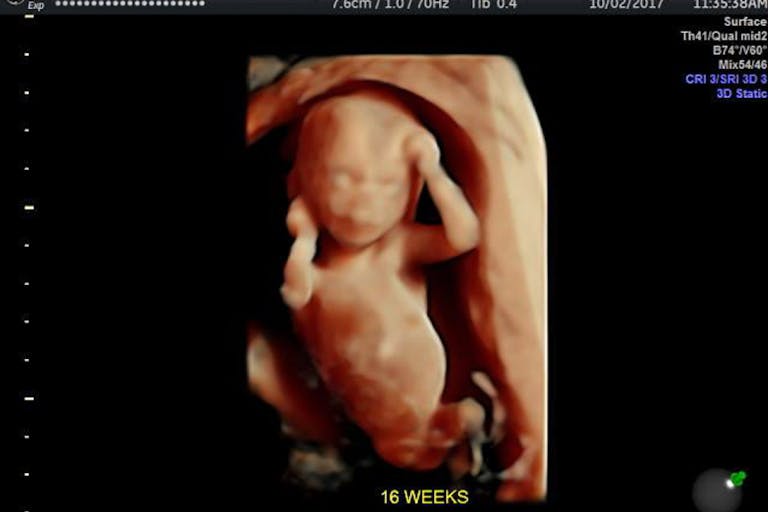

D&E abortions are the most common second trimester abortion procedure, and it’s extraordinarily violent. In it, a preborn child is ripped apart limb from limb, when they are able to feel pain.